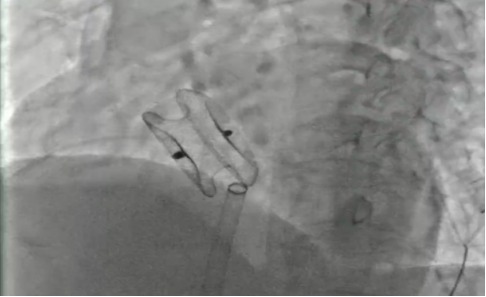

成功封堵

我院心血管內(nèi)科介入團隊經(jīng)詳細(xì)評估后,開展了充分的術(shù)前討論,決定為張阿姨行“室上速射頻消融手術(shù)+房間隔缺損封堵術(shù)”的一站式手術(shù)。該方案通過介入微創(chuàng)實施,一個小穿刺點傷口完成兩個手術(shù),不僅大大減輕分次手術(shù)給患者帶來的痛苦及經(jīng)濟負(fù)擔(dān),而且術(shù)后恢復(fù)快。最終手術(shù)成功實施,術(shù)后第二天患者即可下床活動。